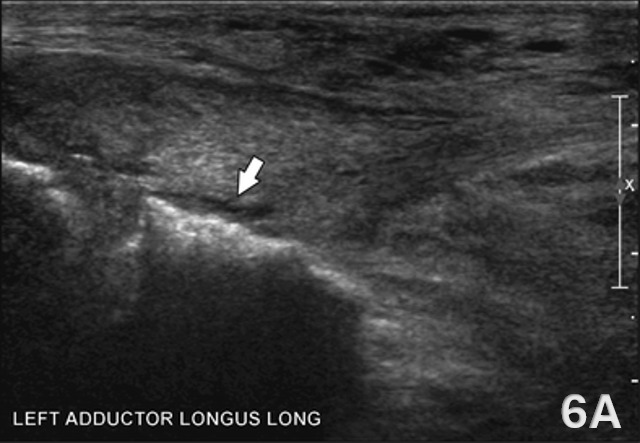

Figure 6. Adductor Longus Tendinosis in LAX

Figure 6A shows a chronic adductor longus tendinopathy in a 36-year-old male runner with a history of bilateral groin pain. LAX ultrasound imaging of the contralateral left adductor longus demonstrates a thickened, hypoechoic tendon origin consistent with tendinosis, accompanied by a small focal detachment at the pubic attachment (arrow). The adjacent adductor brevis, adductor magnus, gracilis, and pectineus muscles appear normal in echotexture and architecture, confirming that the pathology is isolated to the adductor longus.13